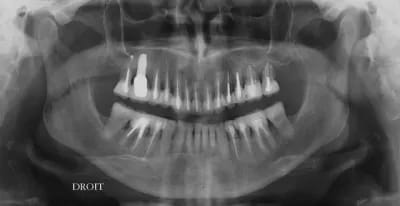

Patiente venant pour son bridge 44-(43)-42-41 mobile avec abces.

Vous lui proposeriez quoi? et comment lui présenteriez vous les choses?

Elle n'a absolument pas conscience de son probleme sur 33

Je pensais lui poser 3 implants en 43-41-33 et tout extraire le bloc incisivo canin mandibulaire...avec des extractions stratégiques de 31 et 32. (en plus du traitement parodontal pour la poche en distal de 35)

Pour moi c'est sans espoir... et extractions 42/41 et 33

En fait c’est le même problème qui se répète d’abord la 43 et ensuite la 33.

J'ai vraiment un doute pour la 33 que je tenterais car il n'y a jamais rien eu de fait, il y aurait un traitement endodontique j'aurais dit avulsion; 41 et 42 si c'est très mobile c'est vrai que ça sent mauvais.

Si vraiment c'est foutu pour toi (dans ce cas là ton plan de traitement est évidemment cohérent), tu lui montres les radios, le niveau osseux, la taille de la lésion. Ca devrait suffire pour qu'elle comprenne les extractions 41, 42, 33.

Pour 31 et 32 tu lui dit simplement que vu le niveau osseux elles seront perdues dans quelques années et que tu auras un résultat plus prévisible, plus esthétique, plus économique et plus durable si on choisit l'avulsion maintenant pour un bridge implanto-porté.

Alors que si on attends, cela veut dire à la perte de 31-32 poser de nouveaux implants, ou exploiter des implants qui n'auront pas été posés de manière optimale en refaisant un bridge: nouveaux travaux, coût plus important, période d'édentement ou d'amovible.

Dans un cas comme celui-ci, considérer que les problèmes s’arrêtent à 44-(43)-42-41 et à la poche en distal de 35 me semble particulièrement simpliste.

bien sûr elle n'a aucun problème de santé, non fumeuse, hygiène parfaite.... donc, recherche des facteurs qui ont conduit à cet état, traiter les causes, contention endo, paro , donc traitement global pour assainir, équilibrer tout ça, et si besoin d'avulser il sera toujours temps...